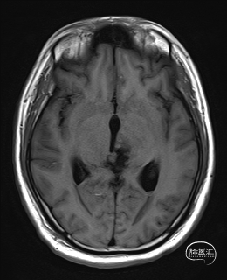

术前MRI检查

术前MRI检查提示左侧丘脑中脑海绵状血管瘤并卒中,梗阻性脑积水;

诊断:1.左侧丘脑中脑海绵状血管瘤并卒中,2.梗阻性脑积水;

年轻患者,较短时间内发生左侧丘脑二次出血,出现右侧面部及上肢麻木,复视,第二次出血后并发梗阻性脑积水,出现头痛。结合病史、神经系统体征、头颅CT及MRI检查,诊断左侧丘脑及中脑CM并卒中、脑积水明确,并导致了神经功能障碍,具备手术指征。

本例患者磁共振检查清晰显示病变位于左侧丘脑中脑区域,且位于丘脑内下方向中脑顶盖延续,病变的上部、前部、外侧部都有重要的神经组织,因此,手术从上方、前方、外侧方向切除病变均难以实施;